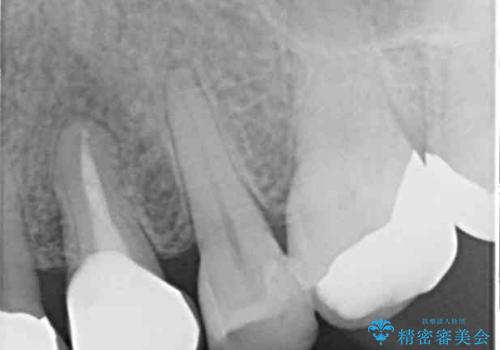

補綴後6ヶ月経過しレントゲンを撮影したところ、歯根周辺に病変認められず、良好な経過をたどっていることが分かりました。

補綴治療では歯の形態を犬歯に近づけ、将来的な歯根への負担を軽減できるようにしました。